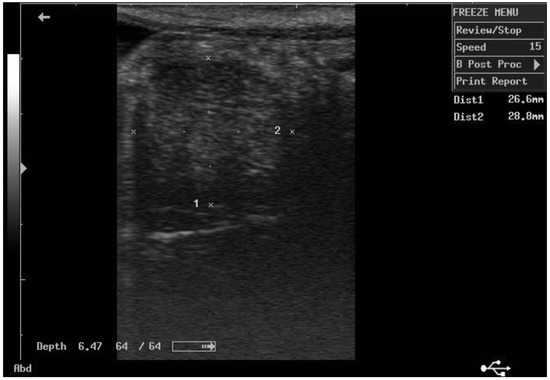

According to ultrasonographic records (Table 1), the mean T diameters did not differ significantly between PPH and NPPH at any time, whereas the mean M diameter of the PPH was larger than the NPPH only until PP Day 7 (Figure 1, Figure 2, Figure 3 and Figure 4). The Bonferroni post hoc test confirmed the ultrasonographic data obtained by ANOVA for repeated measures, when PPH and NPPH were considered across time. Moreover, when only time was assessed, the Bonferroni post hoc test highlighted similar significant changes occurring between PP Days 1–3 and 14–28 (p-value ranging between <0.05 and <0.001) and between PP Days 7 and 14–28 (p-value ranging between <0.05 and <0.01) for the M and CCJ. In relation to T, significant changes were detected among all the times of observation, with p-value ranging between <0.05 and <0.001.

Figure 4. Ultrasound image of the middle tract of the non-post-pregnant uterine horn, at day 14 postpartum.

The diameter of the CCJ in the PPH was not measurable until PP Day 3, then the mean diameter of the CCJ resulted larger in the PPH in comparison to NPPH only at PP Day 7. The first PP ovulation, detected by ultrasonography, occurred 11.9 ± 1.3 days after foaling. At the first PP ovulation, the follicle diameter was 45.1 ± 2.8 mm.

Altogether, the ultrasonographic findings showed that T diameters did not differ significantly between PPH and NPPH at any time, whereas the differences between the mean M and CCJ diameters of the PPH and the NPPH disappeared after PP Day 7, suggesting that uterine involution assessed by ultrasonography could be considered completed by the subsequent observation, performed on PP Day 14. These findings disagree with previous data from the same donkey breed [13], in which, in most jennies, the recovery of the normal uterine diameter was detected by PP Day 21. Even in French donkeys [11], the mean time for uterine involution was about 22 days. Those differences could be attributable to the modality and frequency of ultrasonographic monitoring (equipment, frequency, etc.) and maybe also to the different donkey breed enrolled in the study [11]. The results of the present study are more similar with data reported for the horse mare, in which by PP Days 15–16, an adequate degree of uterine involution was detectable [9,10].